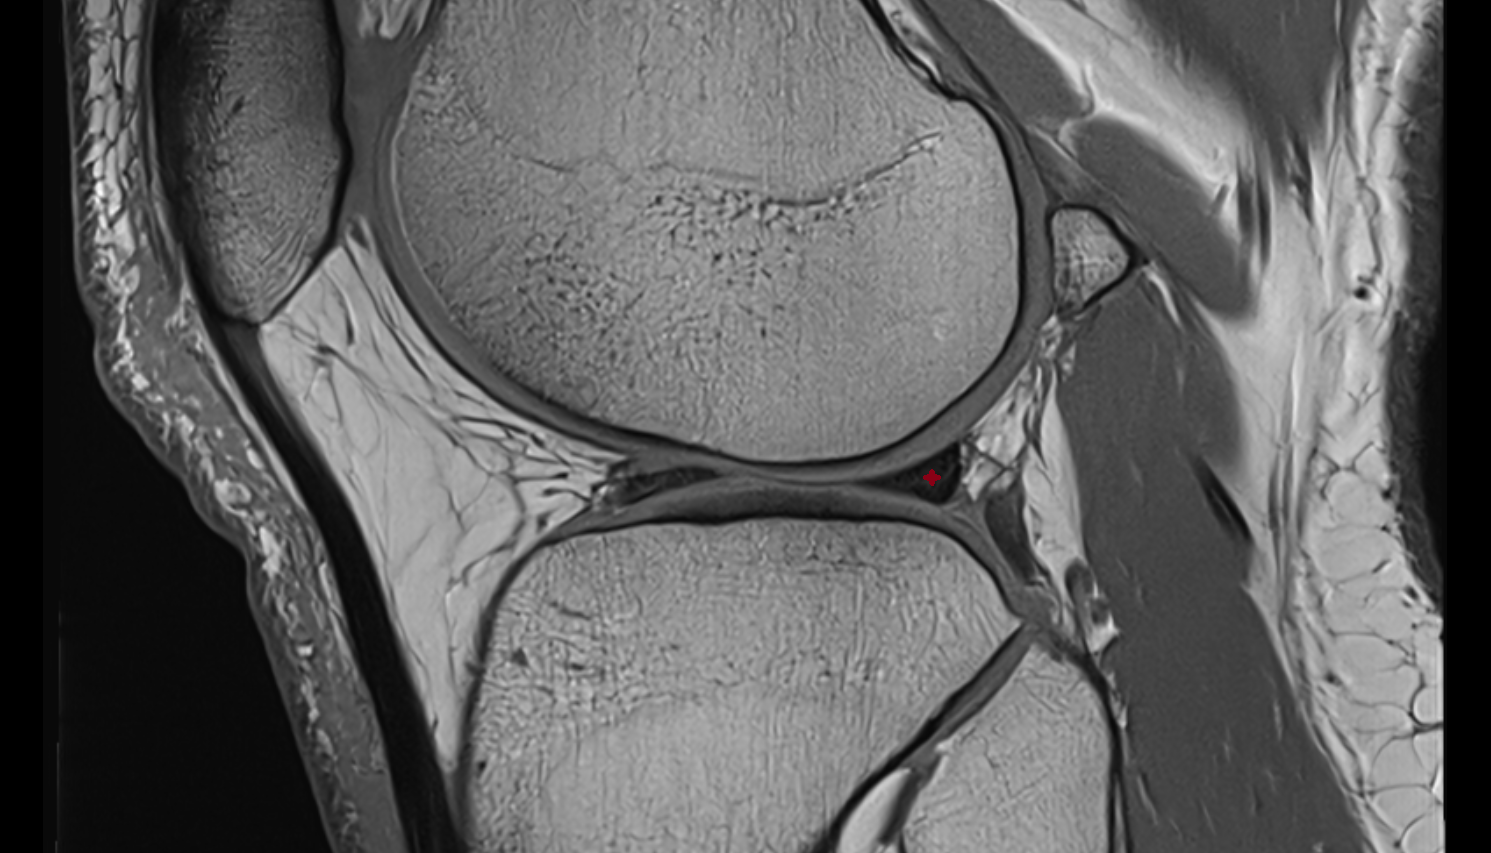

- Anterior cruciate ligament

- Posterior cruciate ligament

- Medial meniscus

- Lateral meniscus

- Knee Joint